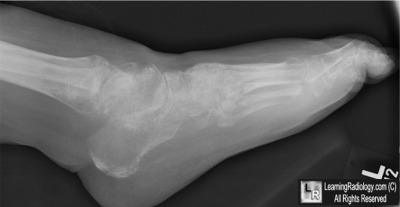

Additional Image-Lateral Radiograph of Same Foot

Lateral Radiograph of Same Foot